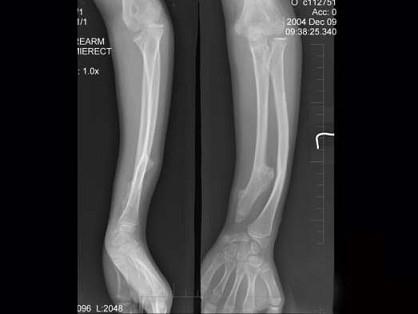

问题 12岁女性患者,左前臂外翻畸形4年,摄片如图所示,最佳的诊断是 ( )

选项 A、软骨发育不全 B、骨折后愈合不良 C、马德隆畸形 D、先天性干骺端发育不全 E、奥利病

答案 C